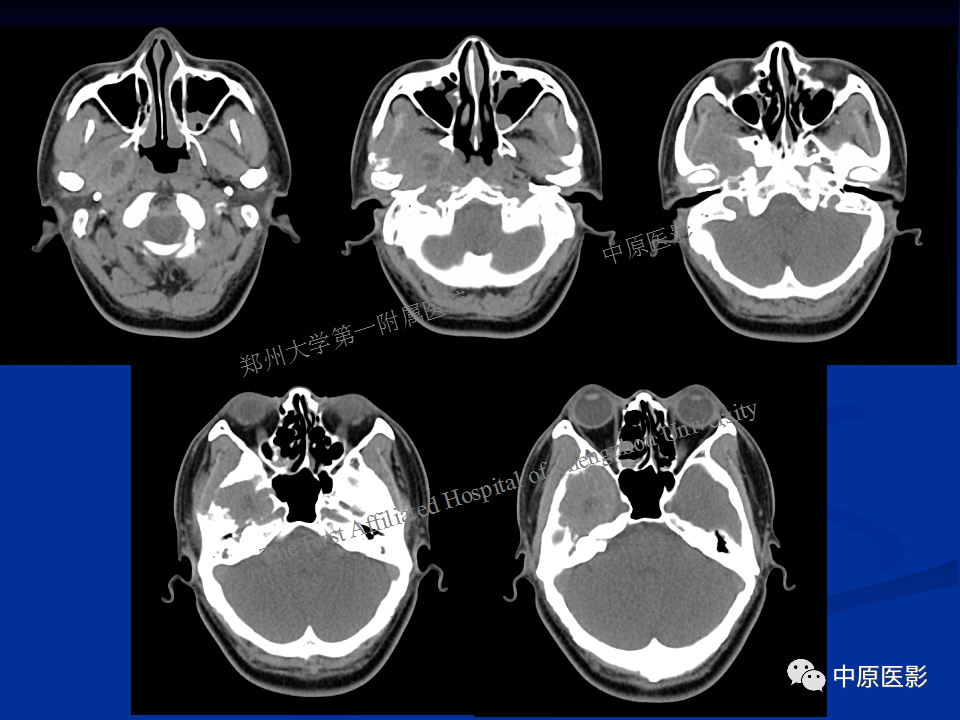

颅底ct

图片尺寸960x720